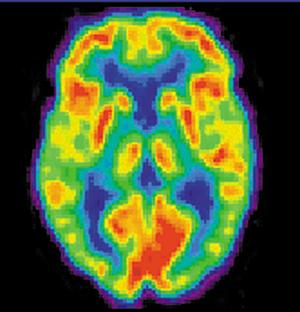

The figure shows brain image of a patient with Alzheimer’s disease.

Figure 22.42 A radiopharmaceutical was used to produce this brain image of a patient with Alzheimer’s disease. Certain features are computer enhanced. (credit: National Institutes of Health)